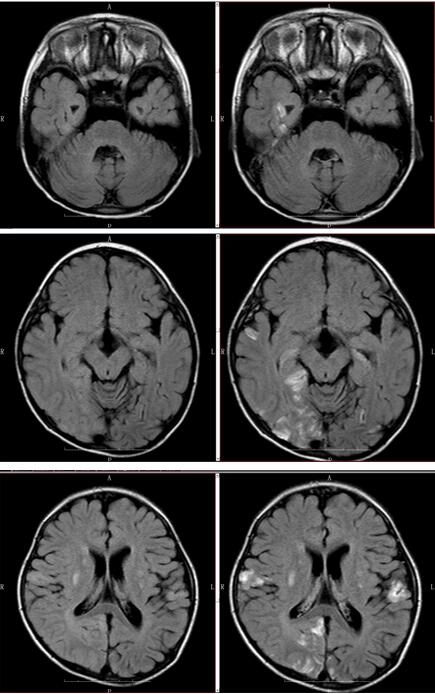

入院后第二日行头颅MR可见双侧基底节区及双侧额颞顶枕叶皮层多发异常信号灶(如下图所示),考虑线粒体脑肌病可能。乳酸测定:乳酸(LAC),5.11mmol/L,高;乳酸(LAC),4.20mmol/(1.33-1.78);患者线粒体基因检测送检指针得6分(计分详见表1),为临床拟诊断为线粒体脑肌病。外院查线粒体基因组全长提示:chrM:m.3243A>G,合子状态为79.9%,来源于母亲(10.2%)。诊断为MELAS型线粒体脑肌病。